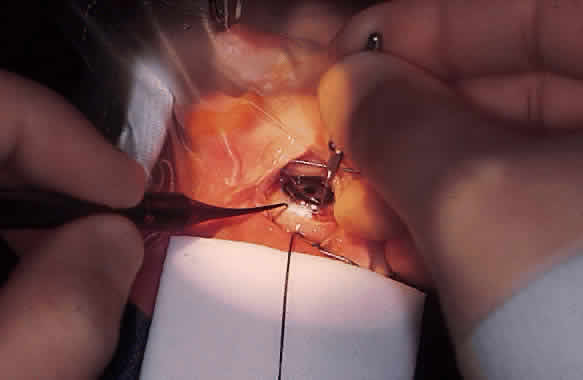

Funduscopy is essential, with both a direct and an indirect ophthalmoscope. The Richardson or Koeppe diagnostic gonioscopy lenses can be of great assistance (Fig. 3). The lens is placed, and then direct ophthalmoscopy is performed through the lens. After this, the periphery should be carefully evaluated with an indirect ophthalmoscope.

Gonioscopy is a mandatory part of the examination under anesthesia. It allows the surgeon to identify the underlying congenital or juvenile glaucoma diagnosis and permits appropriate surgical planning. The Koeppe gonioscopic lens, introduced in 1919,26 has significant advantages over the Zeiss four-mirror or Goldmann three-mirror gonioprism. Chief among these is the ability to compare simultaneously the gonioscopic appearance of two eyes in the same patient (see Fig. 3). The surgeon should be familiar with the gonioscopic findings in primary congenital glaucoma as well as the various secondary glaucomas seen in childhood. Gonioscopic photography can help document the appearance of the anterior chamber angle before and after treatment.